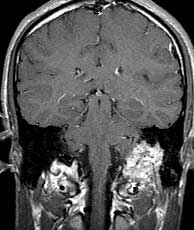

T1 cor post